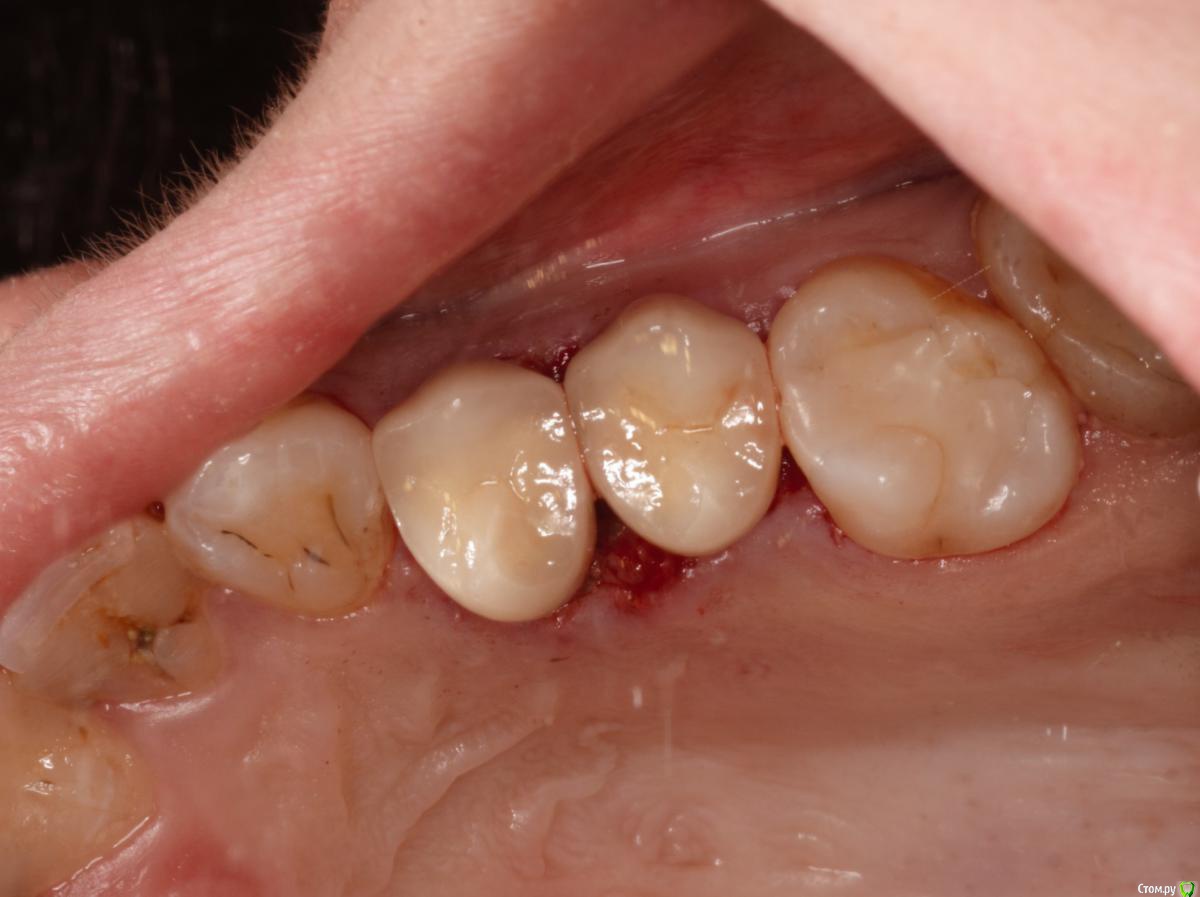

skeettrap Опубликовано 5 июля, 2016 Поделиться Опубликовано 5 июля, 2016 Стандартная ситуация : коллега попросила сделать родственнице (мужа) за неделю - во время краткосрочного визита из Израиля.Исходная ситуация 14,15 сильно разрушены с временными пломбами и наплывшей десной(фото не сделал).На первом этапе сделаны культевые вкладки прямым методом (десну подрезал бором). Постановка вкладок на следующий день, изготовление временных коронок, снятие слепков. Через 2 дня - фиксация. Ссылка на комментарий